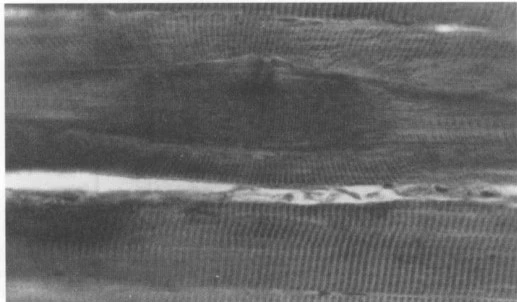

근육은 아주 작은 섬유들의 집합체입니다. 수축과 이완을 하는 과정에서 근섬유가 피로에 빠지게 되면 수축이 된 상태에서 이완이 안되게 됩니다. 위의 사진처럼 꽁꽁 뭉쳐있게 되는데요, 이걸 근막통증증후군이라고 합니다. 근육이 뭉치면 이 부위와 인접부위에 통증을 나타나게 됩니다.

더 정확하게 말하자면 신경계 명령에 의한 지속적인 근육의 수축은 지속적으로 에너지원을 사용하게 됩니다. 그런 와중에서 근수축으로 인한 근육 단면적 증가는 주변 모세혈관을 압박하여 국소적인 허혈성 상태를 만들게 됩니다. 이는 결과적으로 에너지 고갈과 혈류순환 장애는 에너지 위기를 만들어서 근육 수축 이완에 관련된 칼슘의 재흡수를 억제하게 됩니다. 칼슘이 재흡수되지 못하면 근육은 지속적 근수축을 발생시킵니다. 칼슘은 근수축을 명령하는 신경종말물질이니까요. 위의 현상이 지속되다보면 신경전달에 의한 근수축이 아닌 자의적 근수축이 지속적으로 발생하게 됩니다.